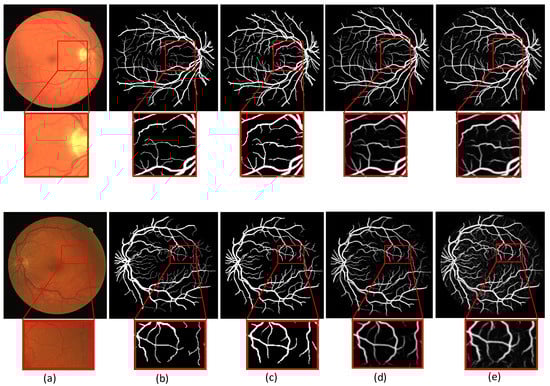

In order to observe the difference of segmentation results more visually, we compare the segmentation visualization images of each model in the ablation experiment. The advantages of MSMB-Net can be seen from the visualized images. Figure 7 and Figure 8 show the visualization results of each model for DRIVE, STARE, CHASE and Drishti-GS1 datasets, respectively.

Figure 7.

Different models at different segmentation results of visualization of the dataset: (a) column is Basic, (b) column is SMCF, (c) column is SMCF + SRL, (d) column is SMCF + MBCM + SRL, (e) column is MSMB-Net.

Figure 7 shows the comparison of the segmentation result images of each model on the DRIVE, STARE and CHASE datasets. In the figures, (1) shows the visualization results of random samples from the DRIVE test dataset, (2) shows the visualization results of random samples from STARE test dataset, and (3) shows the visualization results of random samples from the CHASE test dataset. The yellow boxes in the figure indicate that different network models have different effects on the local segmentation regions of the blood vessels. We can find some broken and mis-segmented vessel segments by zooming in on the yellow box. At the same time, it is observed that the combination of SMCF modules has a certain repair effect on the break of small blood vessels than the combination without these modules. In addition, from the segmentation results, the MSMB-Net model is more accurate for the segmentation of some small blood vessels.